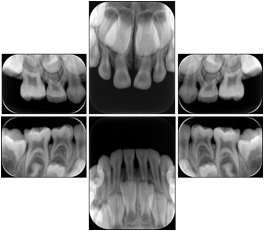

Intra-oral radiography typically involves acquisition of multiple images of various parts of the dentition. Many digital radiographic systems offer customized templates that are used for displaying the images in a study on the screen. These templates may also be referred to as mounts or view sets. The Structured Display Object represents a standard method of encoding and exchanging the layout and intended display of Structured Displays. A structured display object created in this manner could be stored with a study and exchanged with images to allow for complete reproduction of the original exam.

1. A patient visits a General Dentist where a Full Mouth Series Exam with 18 images is acquired. The dentist observes severe bone loss and refers the patient to a Periodontist. The 18 images from the Full Mouth Series along with a Structured Display are copied to a DICOM Interchange CD and sent with the patient to see the specialist. The Periodontist uses the CD to open the exam in his Dental Radiographic Software and consults via phone with the General Dentist. Both are able to observe the same exam showing the images on each user's display using the exact same layout.

Intra-oral Full Mouth Series Structured Display

Figure OO-1. Intra-oral Full Mouth Series Structured Display